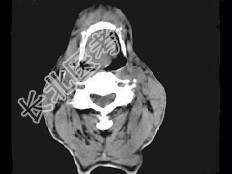

- 单项选择题男,74岁, 咽喉部不适1年余,近两3个月咽喉疼痛, 吞咽困难,CT如图所示, 最可能诊断是 ( )

A、喉癌

B、会厌癌

C、声带癌

D、声门下区癌

E、跨声门型癌